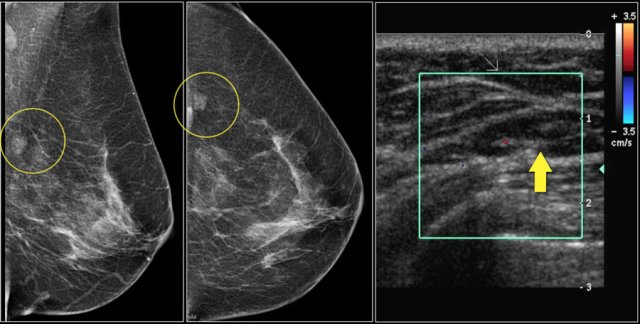

First study the images and describe the findings.

Then continue reading.

The findings are:

- Mass with irregular shape.

- Spiculated margin.

- High density.

- Ultrasound also shows irregular shape with indistinct margin.

This mass is categorized as BI-RADS 5.